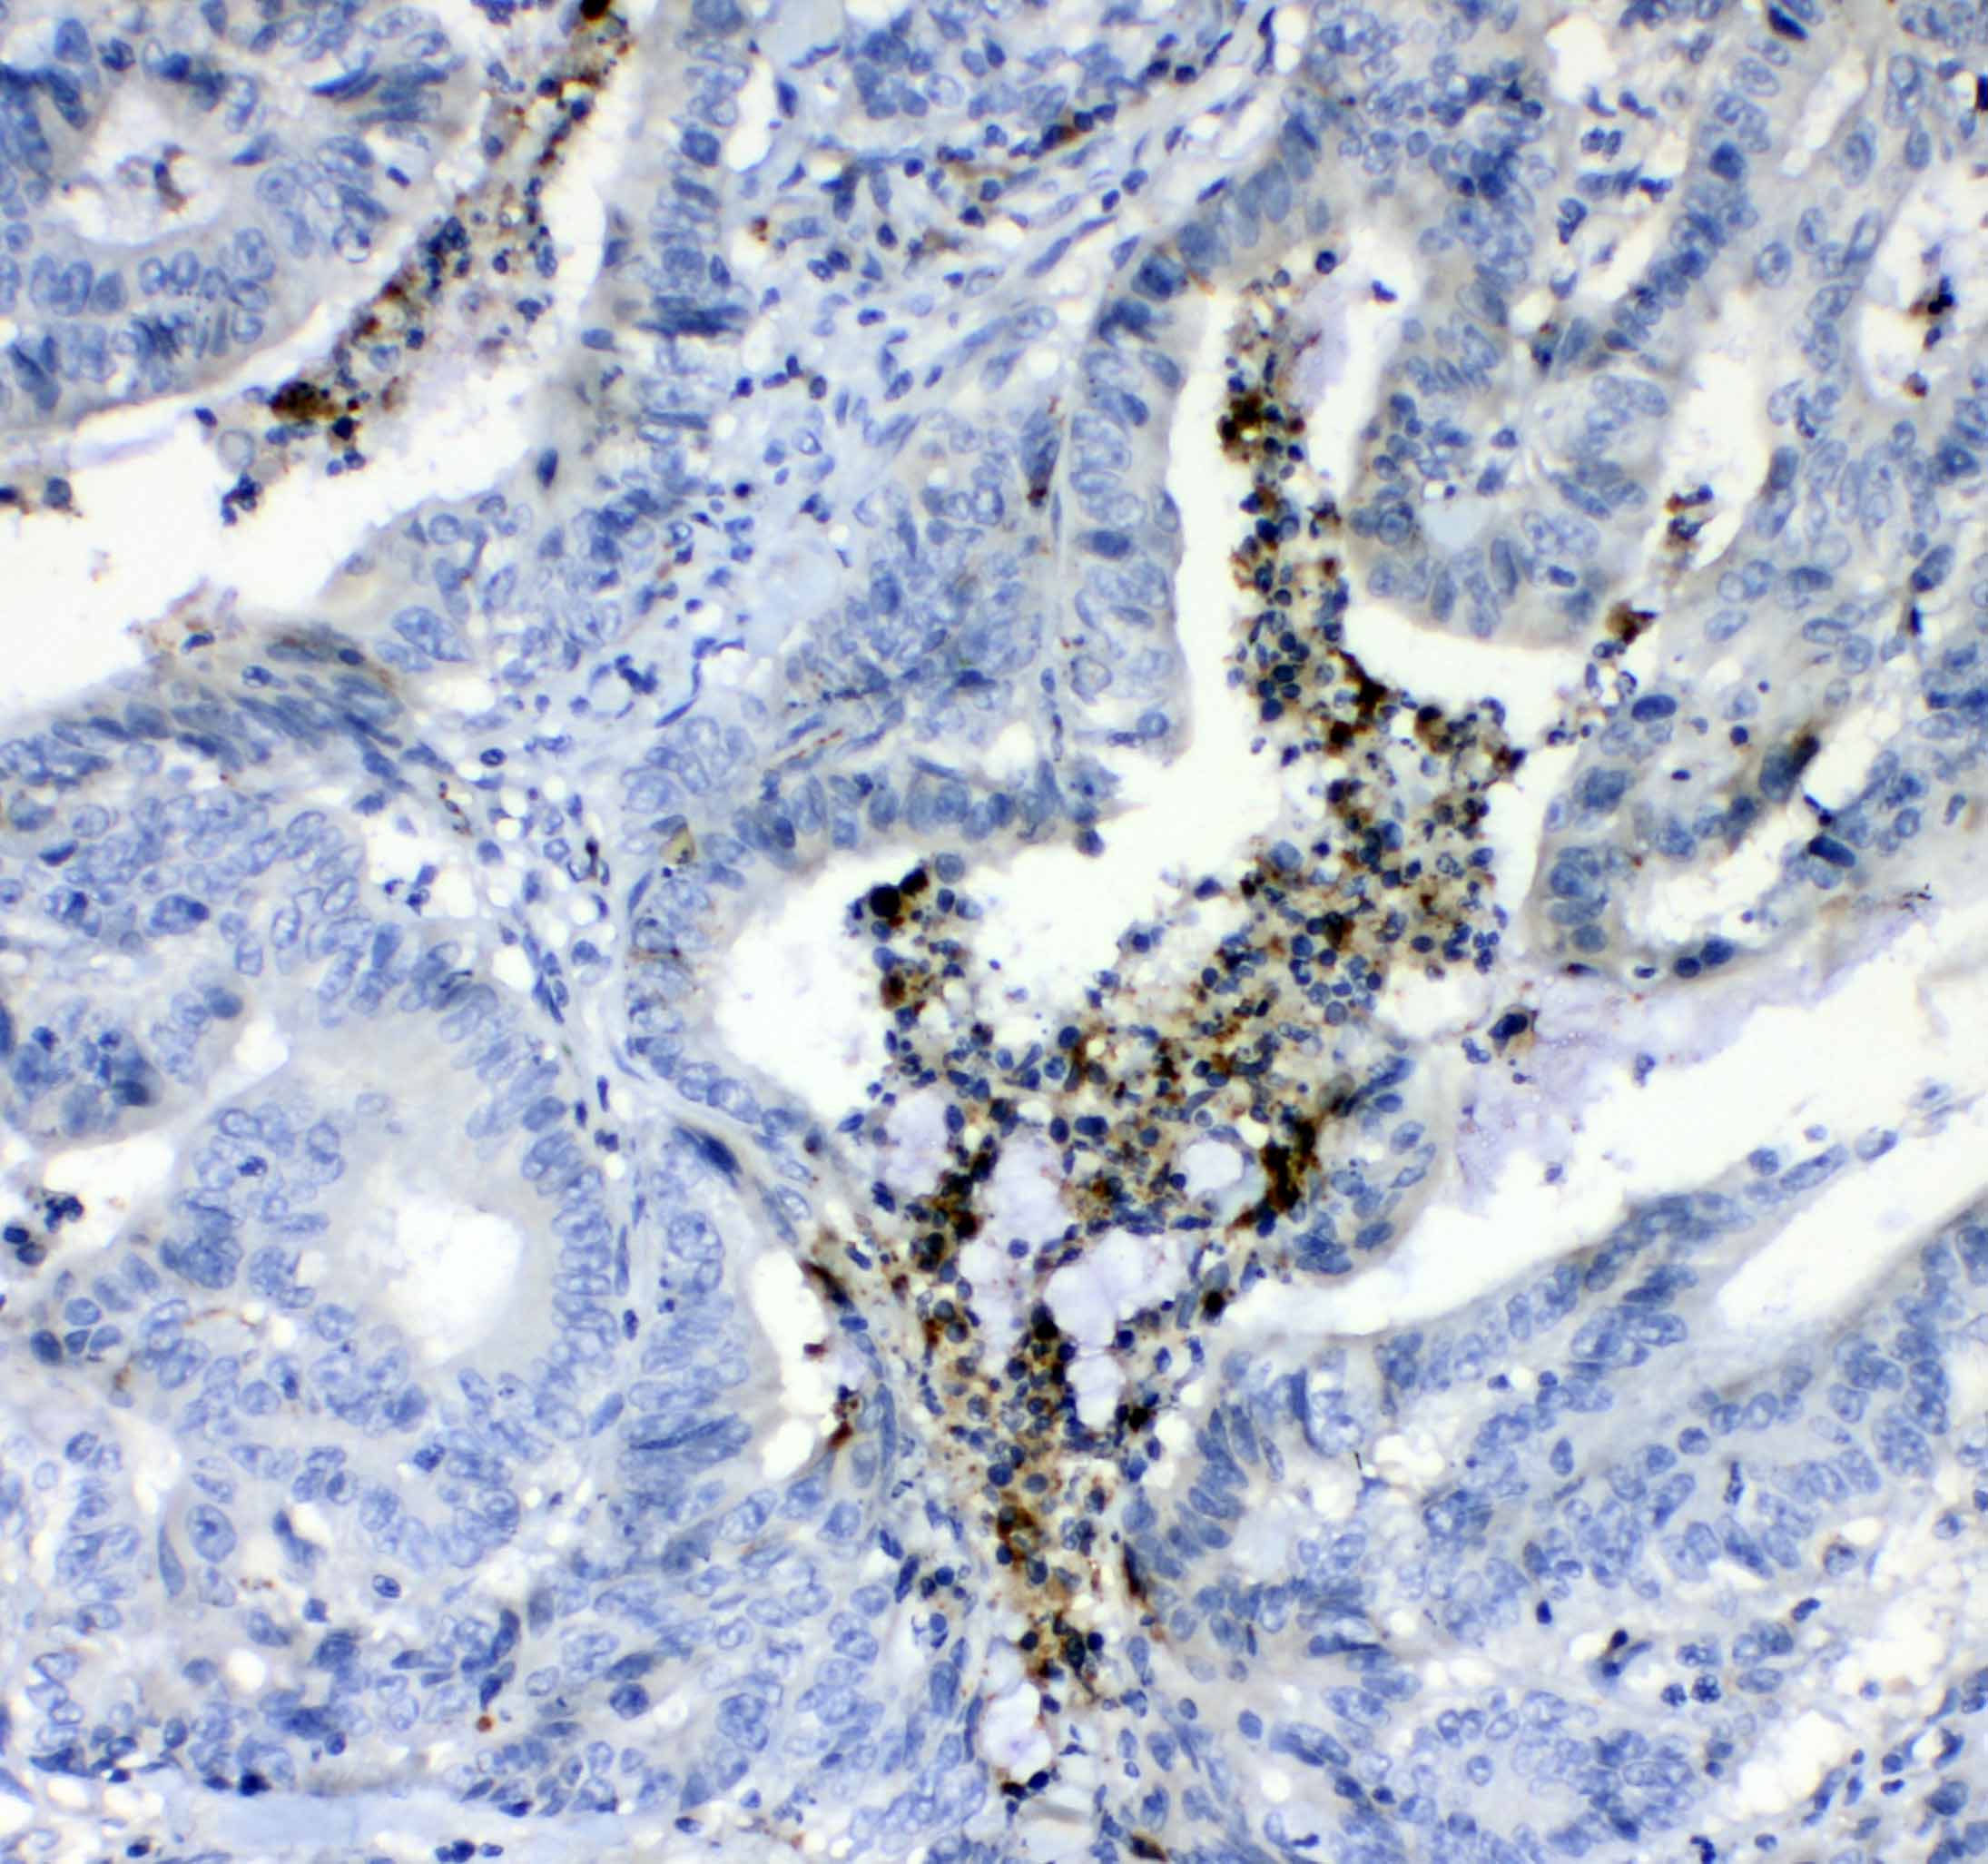

IHC analysis of F2 using anti-F2 antibody (A00044).

F2 was detected in a paraffin-embedded section of human colon cancer tissue. Biotinylated goat anti-rabbit IgG was used as secondary antibody. The tissue section was incubated with rabbit anti-F2 Antibody (A00044) at a dilution of 1:200 and developed using Strepavidin-Biotin-Complex (SABC) (Catalog # SA1022) with DAB (Catalog # AR1027) as the chromogen.